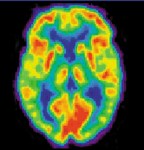

Image: photograph of ‘The punishment of lust’ by Giovanni Segantini in the Walker Gallery, Liverpool.